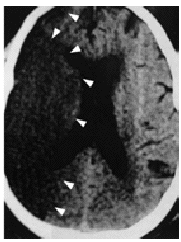

En la figura 1 se aprecia hipodensidad en la región protuberancial izquierda y en hemisferios cerebelosos que comprimen la parte posterior de la cisterna protuberancial. En la figura 2 se observa una hiperdensidad en la salida de la arteria cerebral media (ACM) derecha (a) e hipodensidad de su territorio tributario, y en la figura 3 una hipodensidad de todo el territorio de la ACM derecha. Las flechas de la imagen delimitan la zona isquémica y señalan la hiperdensidad de la ACM, posición M1.

Diagnóstico: infarto de la protuberancia (b), cerebeloso (c) y del territorio de la ACM derecha (d) con visualización de la oclusión de la arteria tributaria de origen embólico.